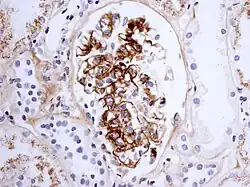

Immune complex glomerulonephritis, as seen in Henoch–Schönlein purpura; this is an example of IgA involvement in a nephropathy

As observed under methods of histopathology, acute necrotizing vasculitis within the affected tissues is observed concomitant to neutrophilic infiltration, along with notable eosinophilic deposition (fibrinoid necrosis). Often, immunofluorescence microscopy can be used to visualize the immune complexes.[11] Skin response to hypersensitivity of this type is referred to as an Arthus reaction and is characterized by local erythema and some induration. Platelet aggregation, especially in microvasculature, can cause localized clot formation, leading to blotchy hemorrhages. This typifies the response to injection of foreign antigen sufficient to lead to the condition of serum sickness.[12]